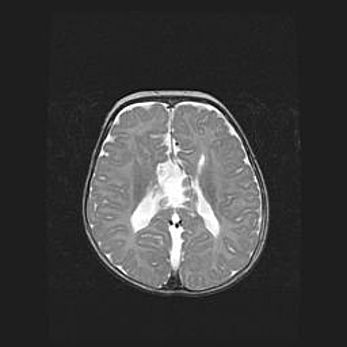

Сообщающаяся гидроцефалия. Кистозная энцефаломаляция головного мозга.

Возраст: 3 месяца 4 дня

Вес: 3100 г

Пол: женский

Окружность головы: 34 см

Срок гестации: 31 неделя

Кистозная энцефаломаляция головного мозга - одна из форм поражения головного мозга в детском возрасте. Характеризуется возникновением множественных и распространённых кист в коре, белом веществе и подкорковых образованиях головного мозга у плодов, новорождённых и детей раннего возраста. Развитие кистозной энцефаломаляции связано с внутриутробной асфиксией и гипотонией, родовой травмой, тромбозом синусов, пороками развития сосудов, инфекциями, сепсисом и другими причинами. Наиболее значимые инфекционные агенты: вирусы простого герпеса, цитомегалии, краснухи, токсоплазмы, энтеробактерии, золотистый стафилококк и другие.